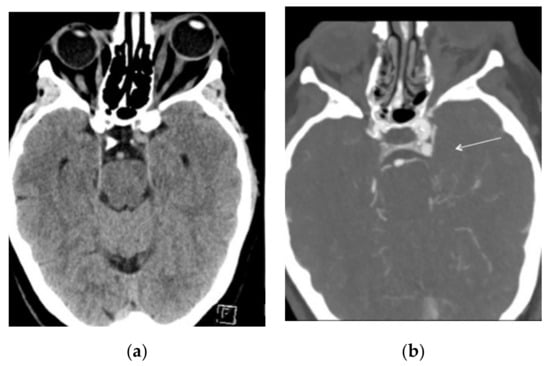

Intracranial CT angiography (Siemens Somatom Definition Flash, 80–100 kV, 151–159 mAs, 0.6 mm thick slices and 512 × 512 matrix) demonstrated an anomalous small venous pouch on the posterior aspect of the left cavernous sinus (Figure 2a,b).

Figure 2. (a) CT scan on admission showing left exophthalmos with hypertrophic extrinsic ocular muscles. (b) CT angio on the same day demonstrating a small venous pouch on the posterior aspect of the left cavernous sinus (white arrow).